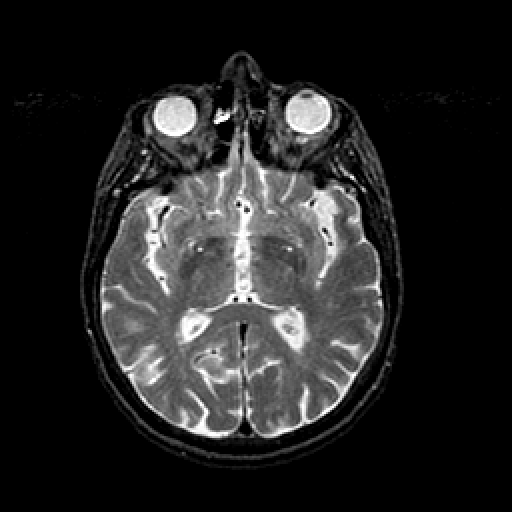

T2-weighted structural MR: Slice 26

Slice 26